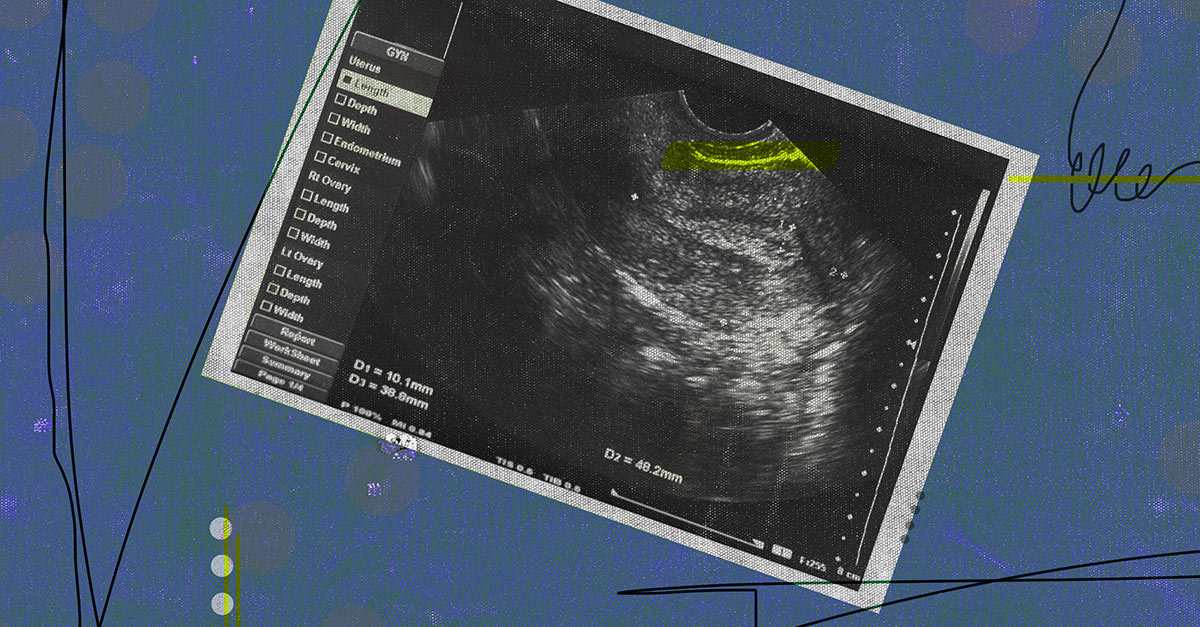

Ever wonder what the dark line is that appears on the screen when you have an ultrasound? Well, that line is actually known as the "endometrial stripe," and no, it doesn't have anything to do with endometriosis (although people often get them mixed up).

What is it? The lining of your uterus is called the endometrium or endometrial lining. This is a complex structure that allows for the implantation of embryos and aids pregnancy. Although tissue similar to the endometrium can grow outside the uterus, which is when conditions like endometriosis occur, the endometrial stripe refers only to that particular thick line you see on a scan.

According to an article published in the RadioGraphics journal, the average measurements of the endometrium can be 2 to 4 millimeters (mm) during your period, 5 to 7 mm during the early stage of your cycle (early proliferative phase) and up to 11 mm in the late stage (late proliferative phase). In the secretory phase, the thickness of the stripe can go up to 16 mm.

Uterine cancer is one of the main types of cancer that affects women's reproductive organs, according to the Centers for Disease Control and Prevention (CDC). Uterine cancer is most commonly found in postmenopausal women and its symptoms include abnormal bleeding and discharge. If an ultrasound technician finds that your endometrial stripe is unusually thick (typically, more than 11 mm), they may refer you to a gynecologist for further testing to rule out endometrial cancer.